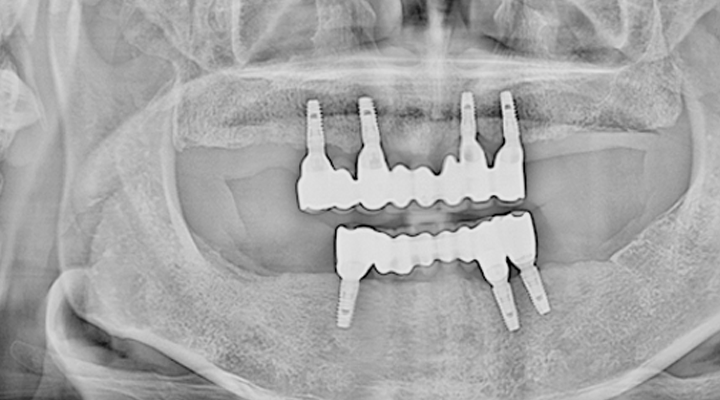

여러 개의 임플란트를 심은 뒤, 그 사이를 금속 막대로 연결해 튼튼한 지지대를

만들고, 그 위에 틀니를 안정적으로 고정하는 방식입니다.